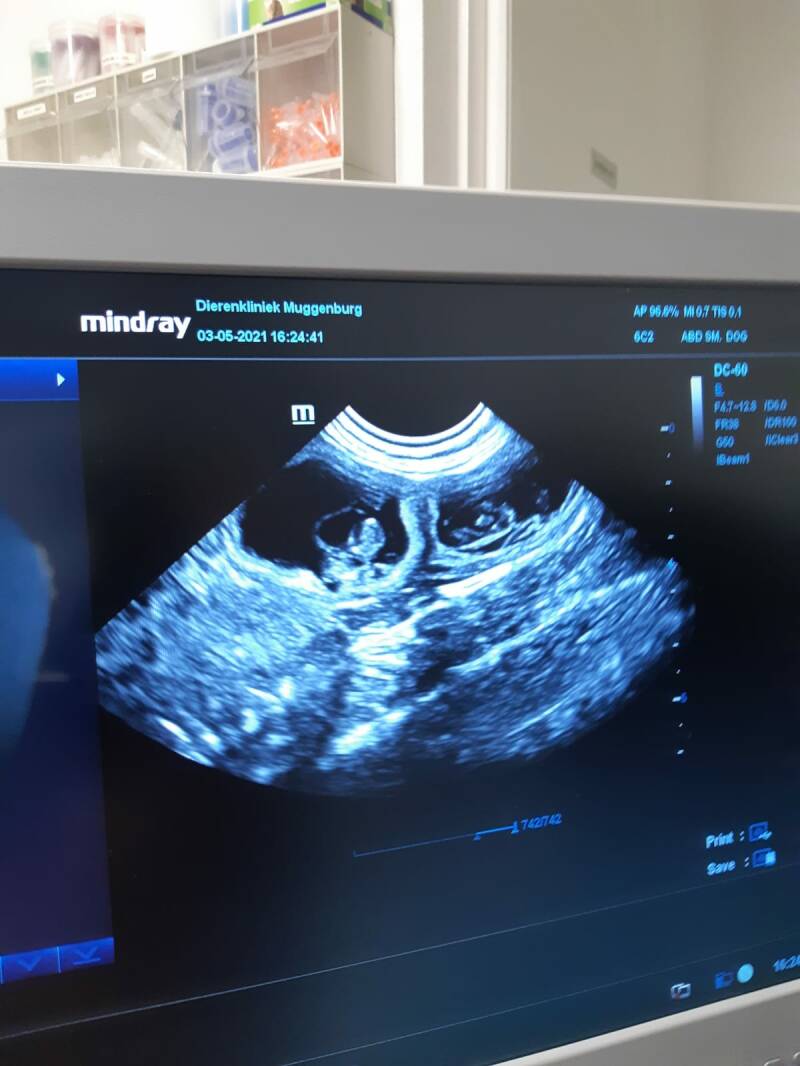

03-05-2021

We zijn vandaag bij de dierenarts geweest en hebben een echo laten maken vorige keer was het niet gelukt en bleek Lois leeg te zijn. Gelukkig mogen we nu vertellen dat lois 4 kittens mag verwachten de hartjes waren goed te horen. Ook vond de dierenarts een leeg vruchtzakje die zich niet heeft ontwikkeld